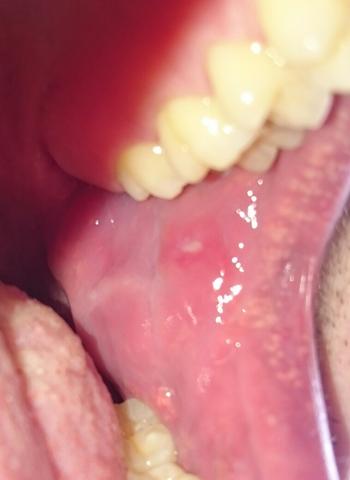

Fieberblasen oder Fieberbläschen können dazu führen dass schmerzhafte weiße Beulen unter Ihrer Zunge auf Ihren Lippen und auf der Innenseite Ihrer Wangen auftreten. Ein wichtiges Stomatitis-Virus ist das Herpes simplex Virus HSV 1 welches bei Kindern die Mundfäule Stomatitis aphtosa hervorruft. Herpes ist hochansteckend Aphthen dagegen nicht.

Beispiel für eine virale Ursache ist die sogenannte Herpes-simplex-Infektion. Sind Aphten wie Herpes. Die herpesartigen Blasen verbreiten sich vor allem auf der Innenseite der Lippe wachsen dort in großer Anzahl und schmerzen erheblich.

Herpes unterscheidet sich auch optisch von Aphthen. Manchmal entstehen Aphthen an der Zungenunterfläche oder am Zungenbändchen von kleinen Kindern wenn diese häufig mit herausgestreckter Zunge husten - so. Ein wohltuendes Mundwasser bei Zungenherpes können Sie selbst herstellen.

Ist Das Auf Dem Bild Herpes Oder Ne Aphte Gesundheit Mund